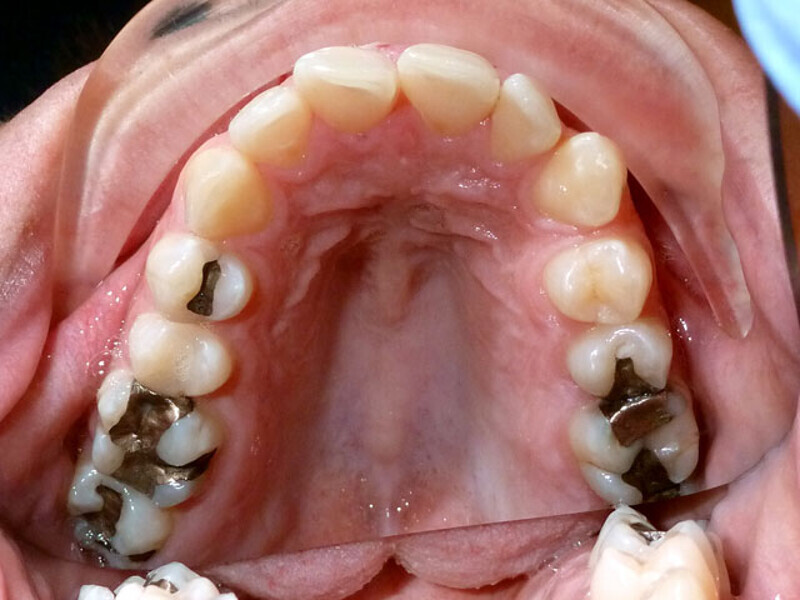

ClearCorrect treatment of crowding